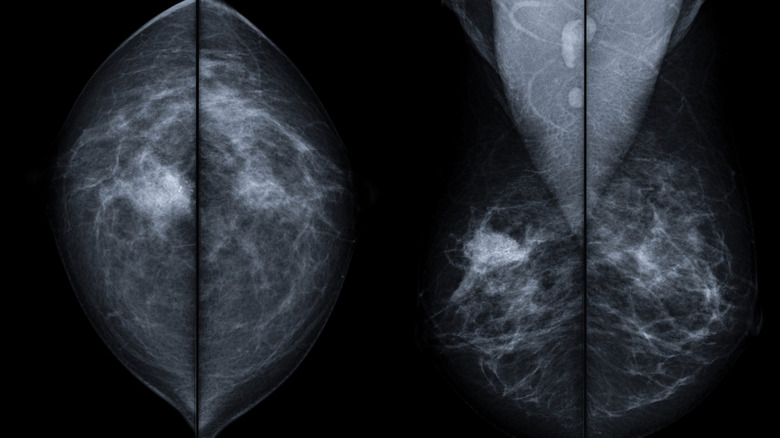

Has your mom ever had breast or ovarian cancer?

Breast and ovarian cancers both have genetic links. Find out whether your mom or other close family members have been diagnosed with breast or ovarian cancer so that you can take preventative action.

Dr. Shainhouse told me, "We now know that carrying a BRCA gene mutation will increase your likelihood of developing breast and ovarian cancer." She continued, "It is important for women to know if they have a family history of breast and/or ovarian cancer in close family members and especially multiple family members, and the age at which they were diagnosed, as this can affect the age at when you might need to begin mammograms, and if you need a more intensive work up."

According to the CDC, one out of 500 women have a BRCA gene mutation, and "If your mother has a BRCA1 or BRCA2 gene mutation, you have a 50 percent chance of having the same gene mutation." Women with a BRCA mutation have a 50 percent risk of contracting breast cancer by the age of 70 and a 30 percent risk of contracting ovarian cancer by the age of 70. By comparison, the numbers for the general population are 7 percent and 1 percent. These numbers aren't meant to freak you out — only to share the point that if you know one of your parents has the BRCA mutation, getting tested will help you take action to protect yourself in the future.